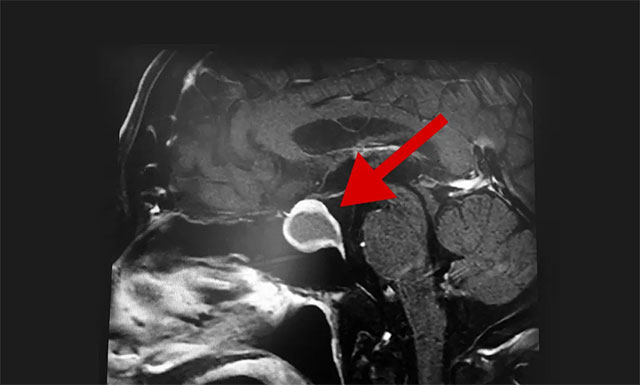

隨后,患者進行了頭部鞍區(qū)MRI平掃+增強,結(jié)果顯示:蝶鞍部顯著擴大,鞍區(qū)見一不規(guī)則腫塊,大小約為2厘米X2.7厘米X1.9厘米,病變向鞍上生長,突入鞍上池,推移視交叉,向下生長,鞍底受壓變薄,與右側(cè)海綿竇部分解剖結(jié)果分界不清。

▲ 影像顯示,腫瘤已嚴重壓迫患者視神經(jīng)

根據(jù)患者檢查結(jié)果,潘仁龍主任介紹,患者之所以視物模糊就是因為垂體腫瘤向鞍上生長,突入鞍上池,壓迫到視神經(jīng)傳導(dǎo)物,而使得患者視物范圍變小,顳側(cè)、鼻側(cè)視野缺損,表現(xiàn)為進行性視力下降、突然頭痛并視力下降。一般1-3cm的大腺瘤或大于3cm的巨大腺瘤,都會引起不同程度的視力問題。